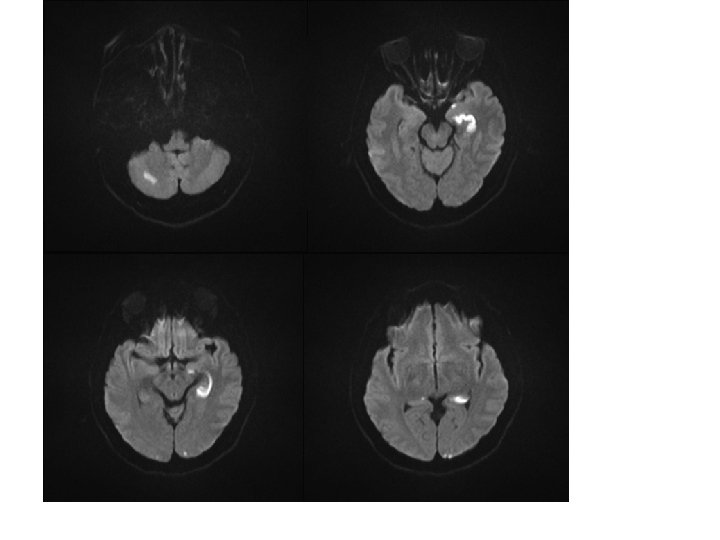

Clinical Manifestations 1) Mild intoxication : nonspecific: headache, nausea, malaise, fatigue, and dizziness 2) Severe intoxications a) Neuropsychiatric symptoms : minor disturbances in attention and cognition to agitation : confusion, hallucination : seizures or frank coma 3) Physical findings : nonspecific a) tachycardia or hyperthermia b) classic “cherry-red” skin : rarely seen c) lactic acidosis, cardiac dysfunction with arrhythmia or ischemia d) pulmonary edema, rhabdomyolysis.

Treatment 1) CO elimination enhancement : oxygen(100%) through tight-fitting mask or endotracheal tube until COHb < 10% 2) Hyperbaric oxygen treament (HBO) a) Indication: COHb > 40% or coma or COHb > 20% in preg with fetal distress b) 3 atm for 30 min → 2 atm for 30 to 60 min c) slow decompression(∵ gas embolism) d) 3 hyperbaric oxygen treatments within 24 hrs of diagnosis reduce neurocognitive sequelae 4) Acid-base and electrolyte balance 5) Steroid and osmotic diuretics : ineffective in cytotoxic(hypoxic) cerebral edema

Prognosis 1) The mortality rate : 30% in severe cases 2) 2/3 of patients who survive ; without sequelae 3) Many of the remainder will suffer from long-term neuropsychiatric symptoms : cognitive dysfunction, abnormal mood or affect, memory disturbances, and other motor or sensory abnormalities